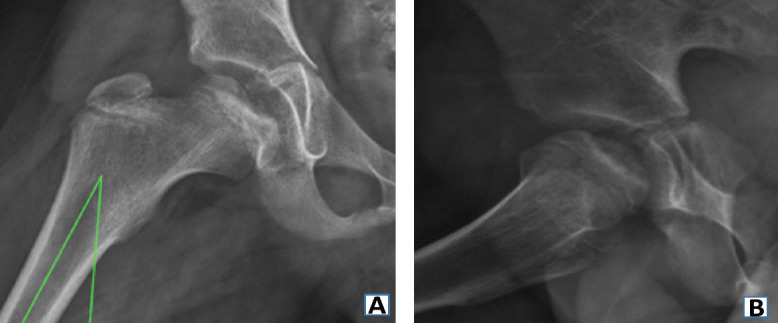

Case report: In this report, we present the case of an 8-year-old Hispanic male who presented with bilateral hip pain unresponsive to conservative treatment and initially managed with the presumptive diagnosis of LCP disease. Due to his persistent hip pain and no improvement on follow-up X-rays and magnetic resonance imaging (MRI), the patient was referred to our hip preservation clinic for further work-up and management recommendations. MRI revealed bilateral OCD lesions of the femoral head secondary to developmental hip dysplasia. The patient underwent bilateral triple PAO for correction of the patient's bilateral hip dysplasia, which resulted in the proper resolution of the femoral head lesions on imaging and eventually resolved the patient's hip pain.